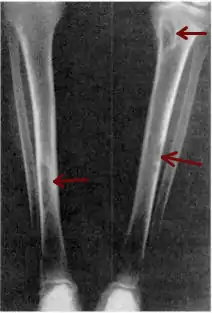

| Osteitis fibrosa cystica of the tibia. Arrows point to the brown tumors which are typically present in bones of people with OFC. | |

Osteitis fibrosa cystica (/ˌɒstiˈaɪtɪs faɪˈbroʊsə ˈsɪstɪkə/ OSS-tee-EYE-tis fy-BROH-sə SIS-tik-ə) is a skeletal disorder resulting in a loss of bone mass, a weakening of the bones as their calcified supporting structures are replaced with fibrous tissue (peritrabecular fibrosis), and the formation of cyst-like brown tumors in and around the bone. Osteitis fibrosis cystica (OFC), also known as osteitis fibrosa, osteodystrophia fibrosa, and von Recklinghausen's disease of bone (not to be confused with von Recklinghausen's disease, neurofibromatosis type I), is caused by hyperparathyroidism, which is a surplus of parathyroid hormone from over-active parathyroid glands. This surplus stimulates the activity of osteoclasts, cells that break down bone, in a process known as osteoclastic bone resorption. The hyperparathyroidism can be triggered by a parathyroid adenoma, hereditary factors, parathyroid carcinoma, or renal osteodystrophy. Osteoclastic bone resorption releases minerals, including calcium, from the bone into the bloodstream, causing both elevated blood calcium levels, and the structural changes which weaken the bone. The symptoms of the disease are the consequences of both the general softening of the bones and the excess calcium in the blood, and include bone fractures, kidney stones, nausea, moth-eaten appearance in the bones, appetite loss, and weight loss.

X-rays may also be used to diagnose the disease. Usually, these X-rays will show extremely thin bones, which are often bowed or fractured. However, such symptoms are also associated with other bone diseases, such as osteopenia or osteoporosis.[29] Generally, the first bones to show symptoms via X-ray are the fingers.[22] Furthermore, brown tumors, especially when manifested on facial bones, can be misdiagnosed as cancerous.[29] Radiographs distinctly show bone resorption and X-rays of the skull may depict an image often described as "ground glass" or "salt and pepper".[30][31] Dental X-rays may also be abnormal.[2]